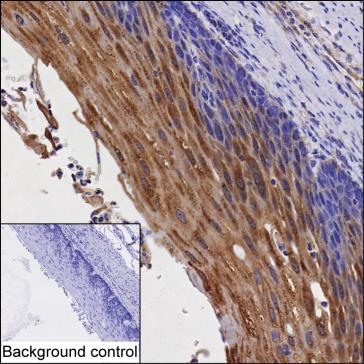

| IHC | 1/50-1/200 | Human,Mouse,Rat |

Studies using GBP6 antibodies have explored its role in diseases such as viral infections, autoimmune disorders, and cancers, where dysregulated GBP expression may influence disease progression. Available as monoclonal or polyclonal versions, these antibodies are validated for techniques like Western blotting, immunohistochemistry, and immunofluorescence. Ongoing research aims to clarify GBP6's precise mechanistic contributions, potentially revealing therapeutic targets for immune-mediated conditions.